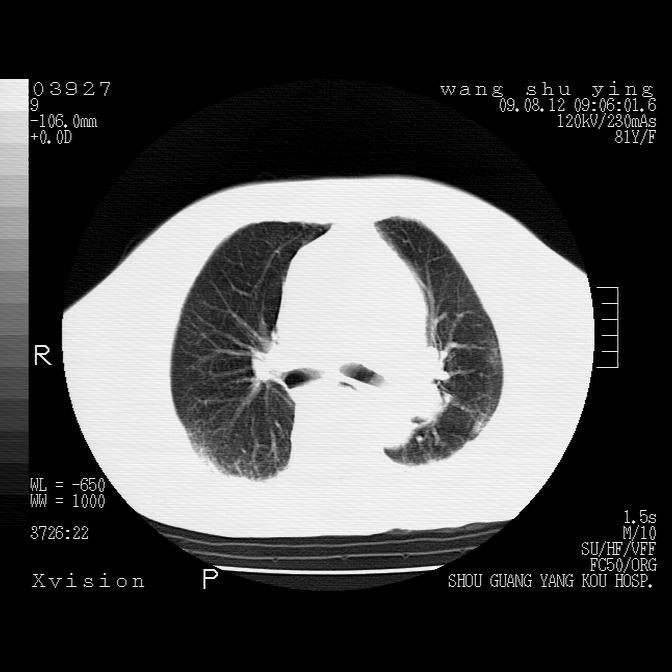

以下是引用帅河马在2009-8-12 12:59:00的发言:[br]两肺感染性病变伴双侧胸膜肥厚。[br]左侧甲状腺腺瘤不除外。[br]腹水+心包积液。[br][br][本贴已被 帅河马 于 2009-8-12 13:14:32 修改过]

以下是引用sdzyy在2009-8-12 18:17:00的发言:[br]两肺感染性病变伴双侧胸膜肥厚。[br]左侧甲状腺腺瘤不除外。[br]腹水+心包积液。[br]支持

以下是引用随光逐影在2009-8-12 19:42:00的发言:[br]1)两肺感染性病变伴双侧胸膜肥厚。2)不排除左侧甲状腺腺瘤。3)肝脏占位性病变;建议行进一步检查。